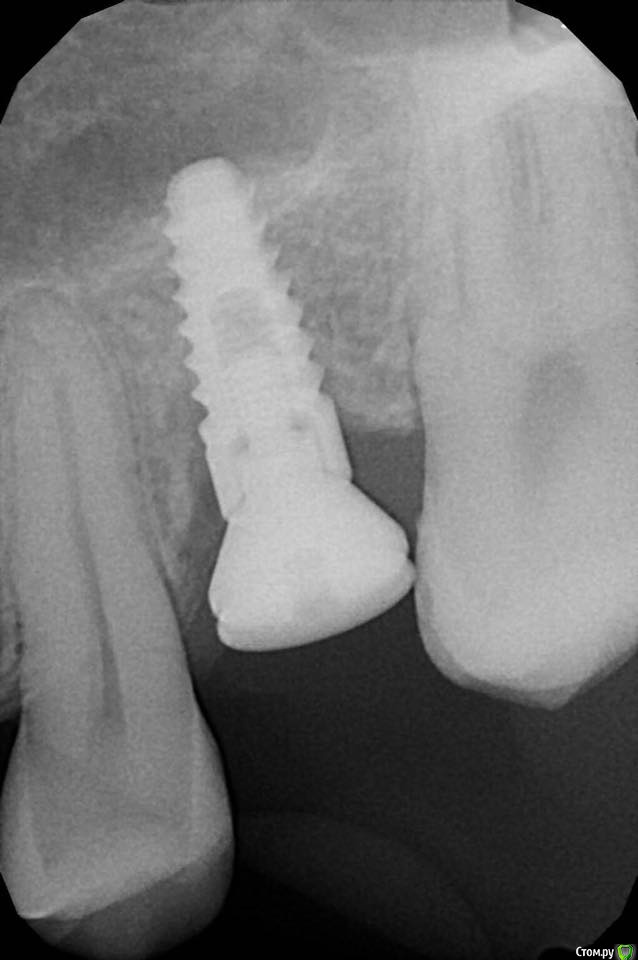

kamranchick Опубликовано 12 сентября, 2018 Автор Поделиться Опубликовано 12 сентября, 2018 Вот) Ссылка на комментарий

Евгений Ходыкин Опубликовано 12 сентября, 2018 Поделиться Опубликовано 12 сентября, 2018 Нуу...в общем... сам всё понимаешь))) Ссылка на комментарий

kamranchick Опубликовано 12 сентября, 2018 Автор Поделиться Опубликовано 12 сентября, 2018 Нуу...в общем... сам всё понимаешь))) что лучше ходить с формиком?)) Ссылка на комментарий